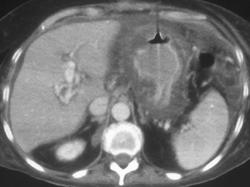

Gastric Varices